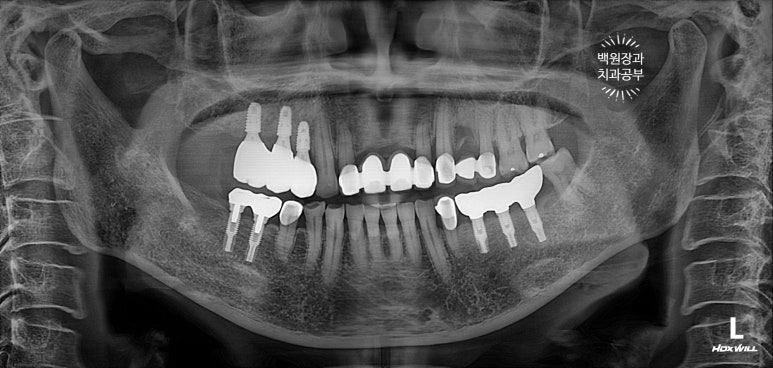

뼈이식을 하고나서 촬영한 치과용 파노라마 사진입니다.

뼈이식재가 엄청나게 잘 위치된 것을 볼 수 있습니다. 마치 뼈가 하나도 없어지지 않았던 것처럼......

정확히 4개월을 기다려 임플란트를 심어드렸습니다.

보시면, 처음 뼈이식했던 것보다는 임플란트가 다소 깊이 위치한 것을 보실 수 있죠?

왜냐면, 아까 얘기했듯이 우리가 사용했던 뼈이식재가 100프로 모두 잇몸뼈가 되지 않기 때문이죠.

드디어 임플란트 재수술이 완료되었습니다.

드디어 임플란트 재수술이 성공적으로 마무리 되었습니다! 정말 긴 시간동안 단 한마디 불평도 없이 잘 따라와주신 환자분께 다시 한 번 감사드립니다 :)

수술 전의 사진과 비교해서 생각보다 임플란트가 원래 자리와 비슷한 레벨에 위치해 있음을 확인할 수 있습니다.

이게 모두 임플란트 제거와 동시에 시행했던 덴티움 뼈이식재를 이용한 치조골 이식술 덕분입니다.

이번 60대 여자 환자분 같은 경우에, 사실 80프로 이상의 임플란트 주변 수직 골소실이 있는 케이스였습니다만.. 정확한 진단과 좋은 재료의 사용으로 정말 좋은 결과를 얻었다고 자부할 수 있습니다.